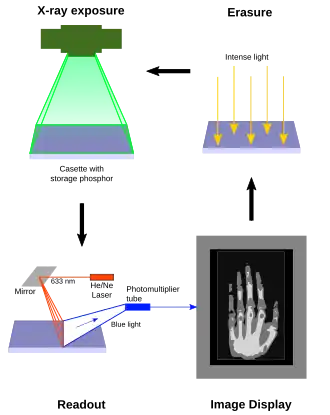

Photostimulated luminescence (PSL) is the release of stored energy within a phosphor by stimulation with visible light, to produce a luminescent signal. X-rays may induce such an energy storage. A plate based on this mechanism is called a photostimulable phosphor (PSP) plate (or imaging plate) and is one type of X-ray detector used in projectional radiography. Creating an image requires illuminating the plate twice: the first exposure, to the radiation of interest, "writes" the image, and a later, second illumination (typically by a visible-wavelength laser) "reads" the image. The device to read such a plate is known as a phosphorimager (occasionally spelled phosphoimager, perhaps reflecting its common application in molecular biology for detecting radiolabeled phosphorylated proteins and nucleic acids).

A lower-frequency light source that is insufficient in energy to create more Eu3+ ions can return the trapped electrons to the conduction band. As these mobilized electrons encounter Eu3+ ions, they release a blue-violet 400 nm luminescence.[4] This light is produced in proportion to the number of trapped electrons, and thus in proportion to the original X-ray signal. It can be collected often by a photomultiplier tube, which is clocked at a specific resolution or pixel capture frequency. The light is thereby converted to an electronic signal and significantly amplified. The electronic signal is then quantized via an ADC to discrete (digital) values for each pixel and placed into the image processor pixel map.

Afterwards, the plates can be "erased," by exposing the plate to room-intensity white light. Thereby, the plate can be used over and over again. Imaging plates can theoretically be re-used thousands of times if they are handled carefully and under certain radiation exposure conditions. PSP plate handling under industrial conditions often results in damage after a few hundred uses. Mechanical damage such as scratches and abrasions are common, as well as radiation fatigue or imprinting due to high energy applications. An image can be erased by simply exposing the plate to a room-level fluorescent light - but more efficient, complete erasure is required to avoid signal carry-over and artifacts. Most laser scanners automatically erase the plate (current technology uses red LED lighting) after laser scanning is complete. The imaging plate can then be re-used.

In phosphor plate radiography, the imaging plate is housed in a special cassette and placed under the body part or object to be examined and the x-ray exposure is made. The imaging plate is then run through a special laser scanner, or CR reader, that reads and converts the image to a digital radiograph. The digital image can then be viewed and enhanced using software that has functions very similar to other conventional digital image-processing software, such as contrast, brightness, filtration and zoom. CR imaging plates (IPs) can be retrofitted to existing exam rooms and used in multiple x-ray sites since IPs are processed through a CR reader (scanner) that can be shared between multiple exam rooms.[6]